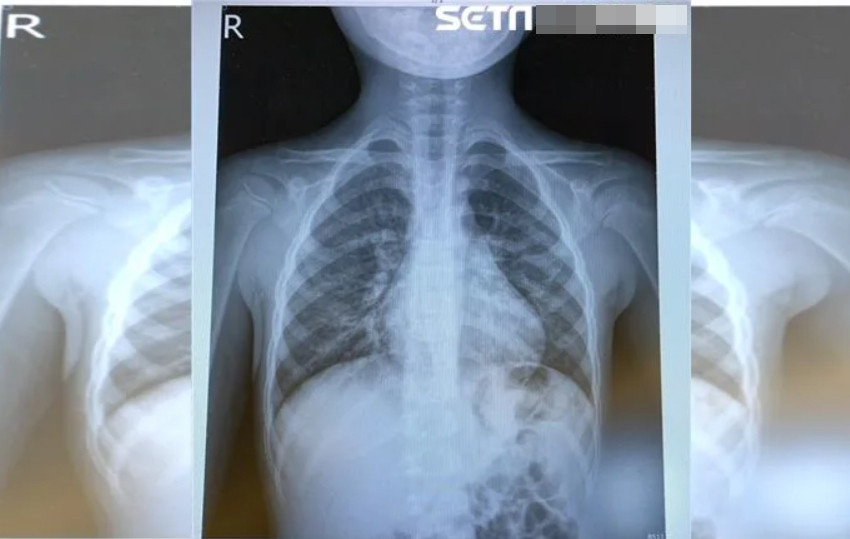

Các triệu chứng phổ biến khi người bệnh nhiễm virus Metapneumovirus là ho, sốt, nghẹt mũi và khó thở. Đây là một trong những nguyên nhân chính gây nên tình trạng nhiễm trùng đường hô hấp cấp tính ở trẻ dưới 5 tuổi. Trong những trường hợp nghiêm trọng, virus này có thể khiến trẻ dưới 5 tuổi bị viêm phế quản hoặc viêm phổi nặng. Đối với người cao tuổi, HMPV có thể gây nhiễm trùng phổi hoặc làm trầm trọng thêm bệnh hen suyễn.

Virus HMPV gây bệnh hô hấp, thường vào mùa đông và đầu xuân, ảnh hưởng nhiều nhất đến trẻ em dưới 5 tuổi, người già, người suy yếu miễn dịch.